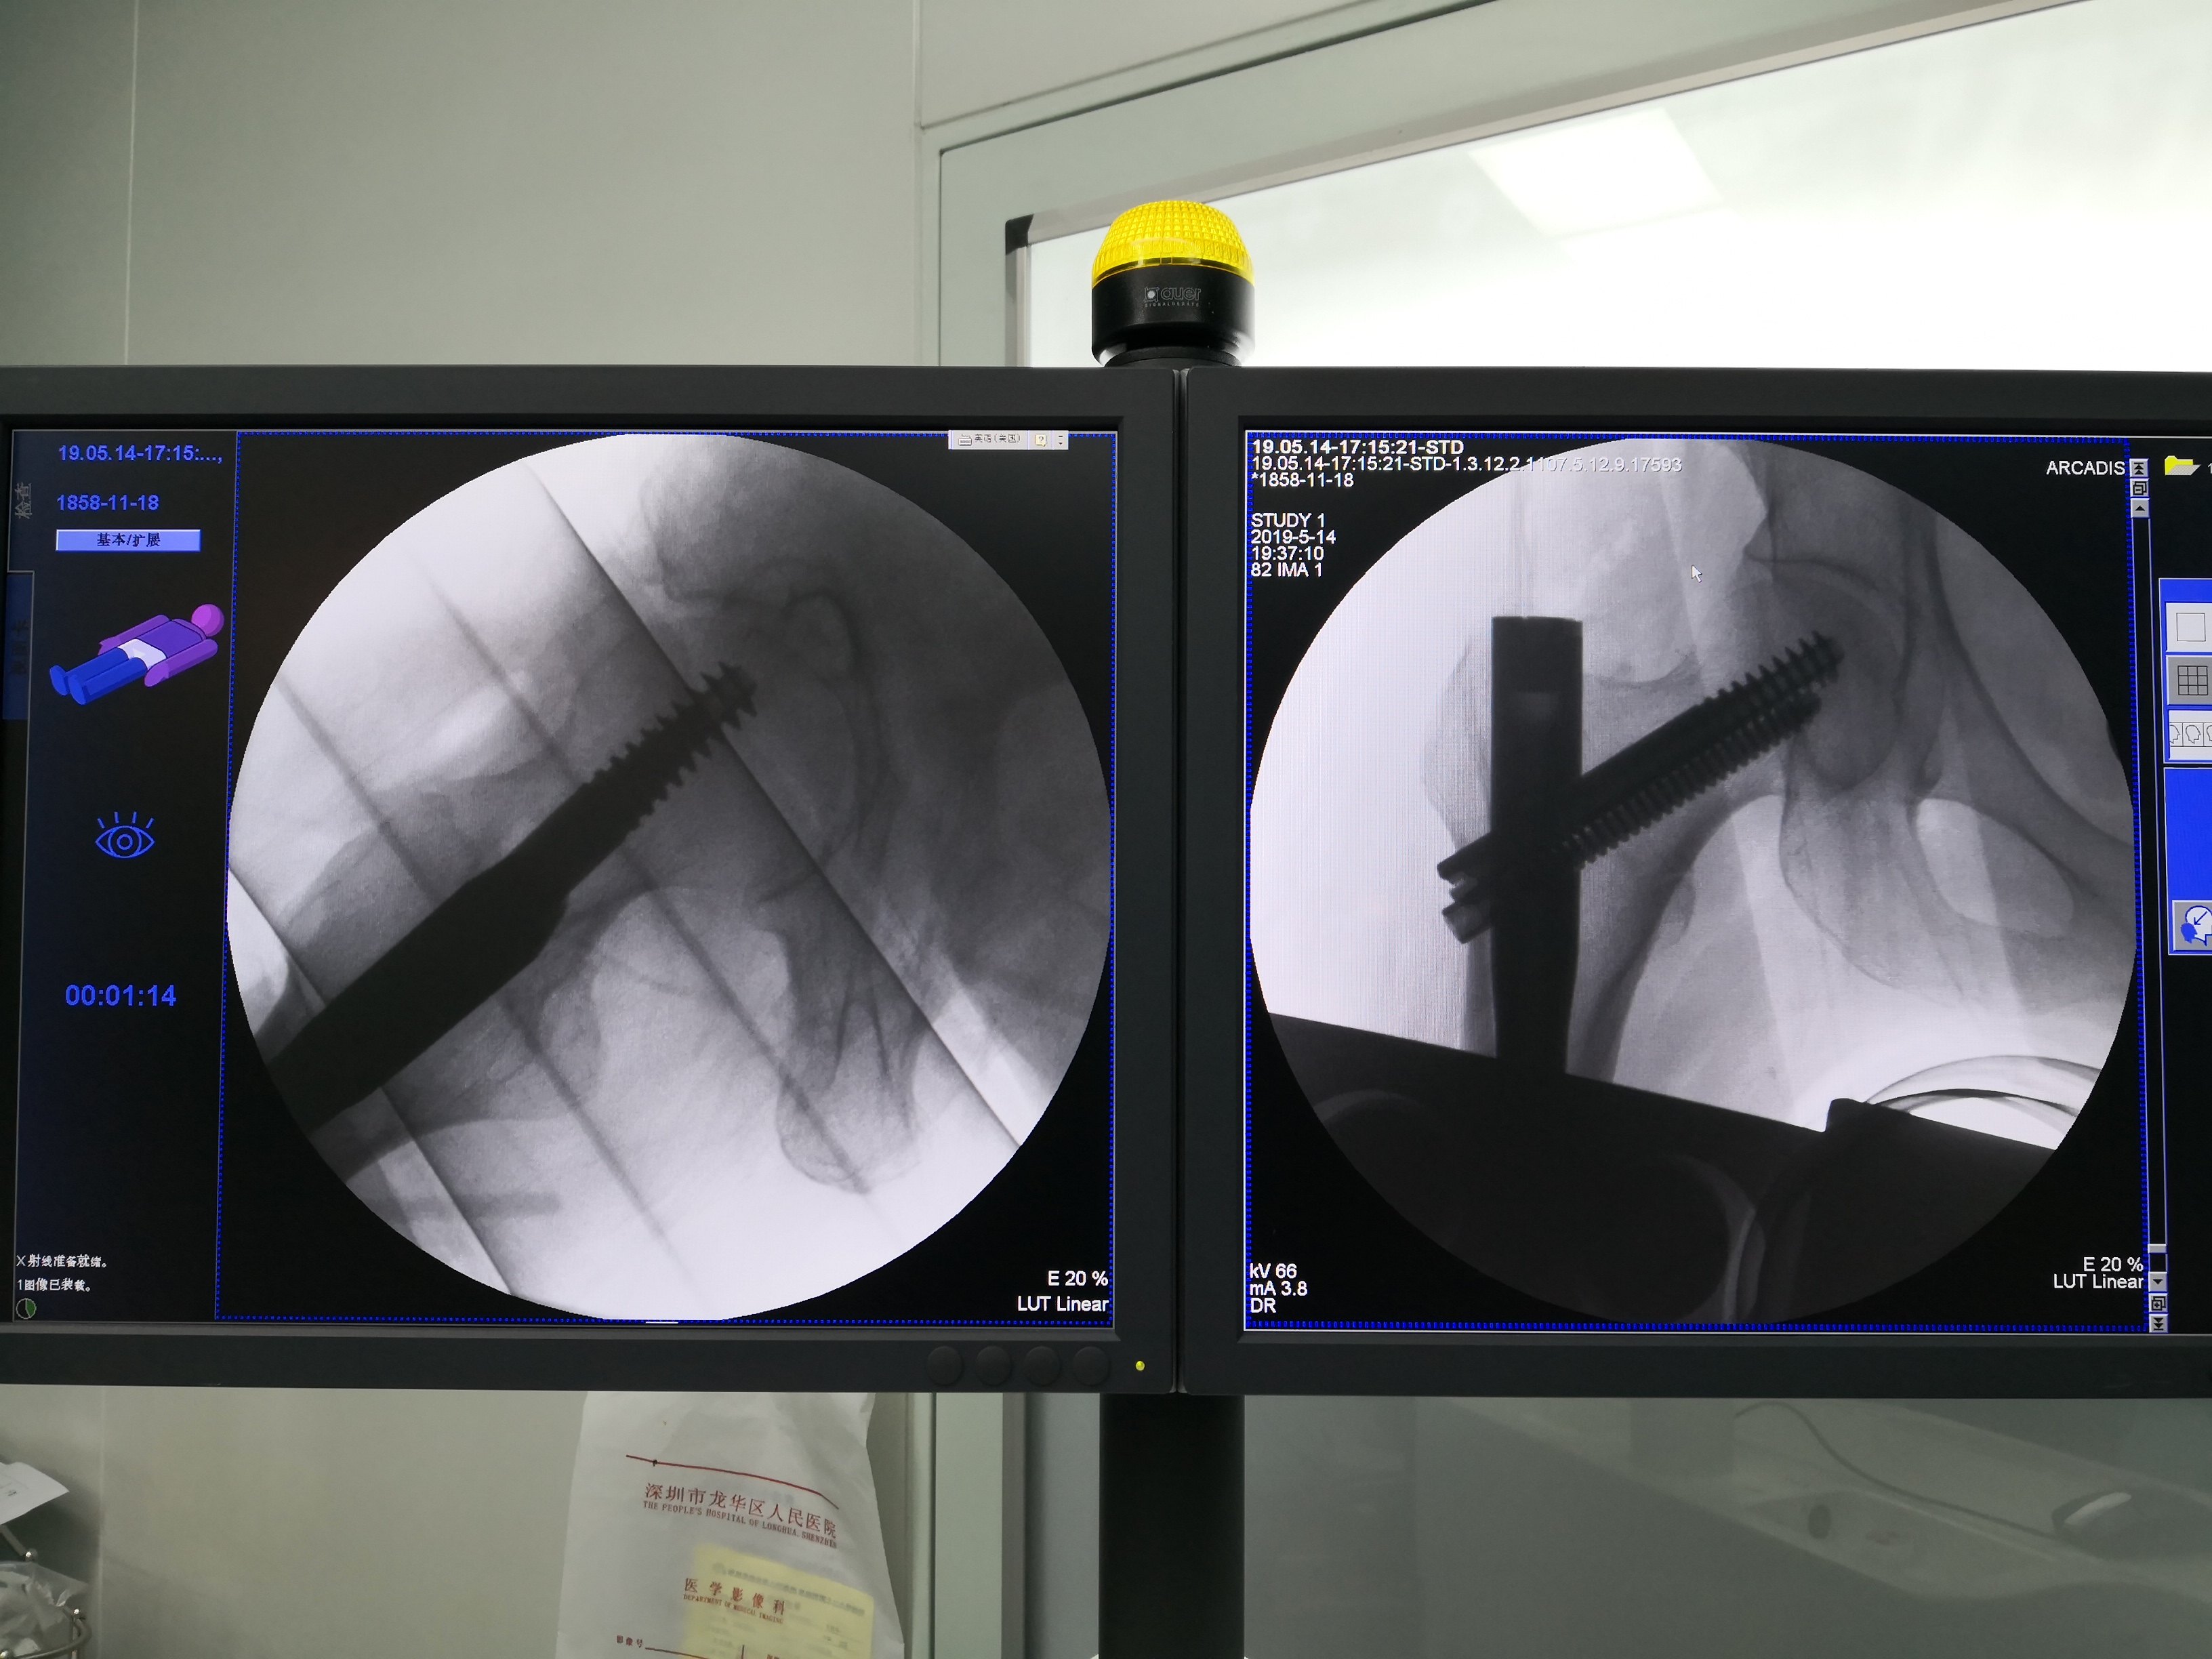

她有1.脑垂体瘤,需要长期吃激素,2.冠心病,心脏放了5个支架,3.2型糖尿病,需要用胰岛素,4.高血压病3级,极高危组,需要吃几种降压药,5.慢性肾功能不全CKD4期,已经到了需要透析的程度,6.脑梗塞,有时有点迷糊,7.双下肢动脉硬化闭塞征。你说这么多病,怎么样办?不管它,卧床休息让骨折自己愈合,行不行。一般家属和医生为了省心和不承担风险,都会选择保守治疗。但这个老人和家属不简单,老人是医学院里的老教授,女儿两个,一个在身边,一个在国外,都主动选择手术治疗,并相信支持我,在国外的女儿因为不在身边,怕我不做手术,还要给我写保证书,出了意外不怪任何人。我知道这是一家懂事理,明是非的人,因为合并这么多病的骨折患者,卧床保守治疗,肯定熬不过3个月,以前曾有类似的、血的教训。做完术前检查,评估风险后进行了股骨近端髓内钉微创手术,手术很顺利,也没进重症监护室,术后3天的一个夜里,老人偷偷溜下了床,被家人发现又把她扶了回去。第二天问她下床不痛吗,她说不痛,就忘记骨折了,说得我们哈哈大笑。因为不痛,我经常让她坐在床边拍背,坐轮椅去晒太阳,术前肾功能差小便很少,术后不知什么原因小便也增多了起来,老人非常高兴,非常乐观,还跟我合了影,留作记念,我是忘不了她的笑容和乐观的。

图片经患者同意才上传。下面我把几个患者的术前骨折片及术中、术后X光片传上来让大家有个认识。

很幸运,5例手术效果都很好。总结一下:股骨转子间骨折是老年髋部骨折最常见的类型,特别是骨质疏松的老年女性,下雨天不要让老人出门,厨房、洗水间要装防滑的软垫,老人房间没洗水间的,要准备尿不湿,很多老人夜尿多,半夜起床上洗水间不敢开灯,怕影响到别人。髋部受伤后要及时就医,拍X光片,确定股骨转子间骨折后不要认为合并有很多慢性病就拒绝手术,能不能手术由医生做完检查后评估,这类手术是能微创做的,使用lNTERTAN髓内钉技术,能让骨折恢复力线,没有疼痛,早期能坐轮椅外出和下床行走,提高生命质量,享受更快乐的晚年。感谢5位并肩作战和支持我的老人家,你们的笑容很灿烂,我会永远记得的!